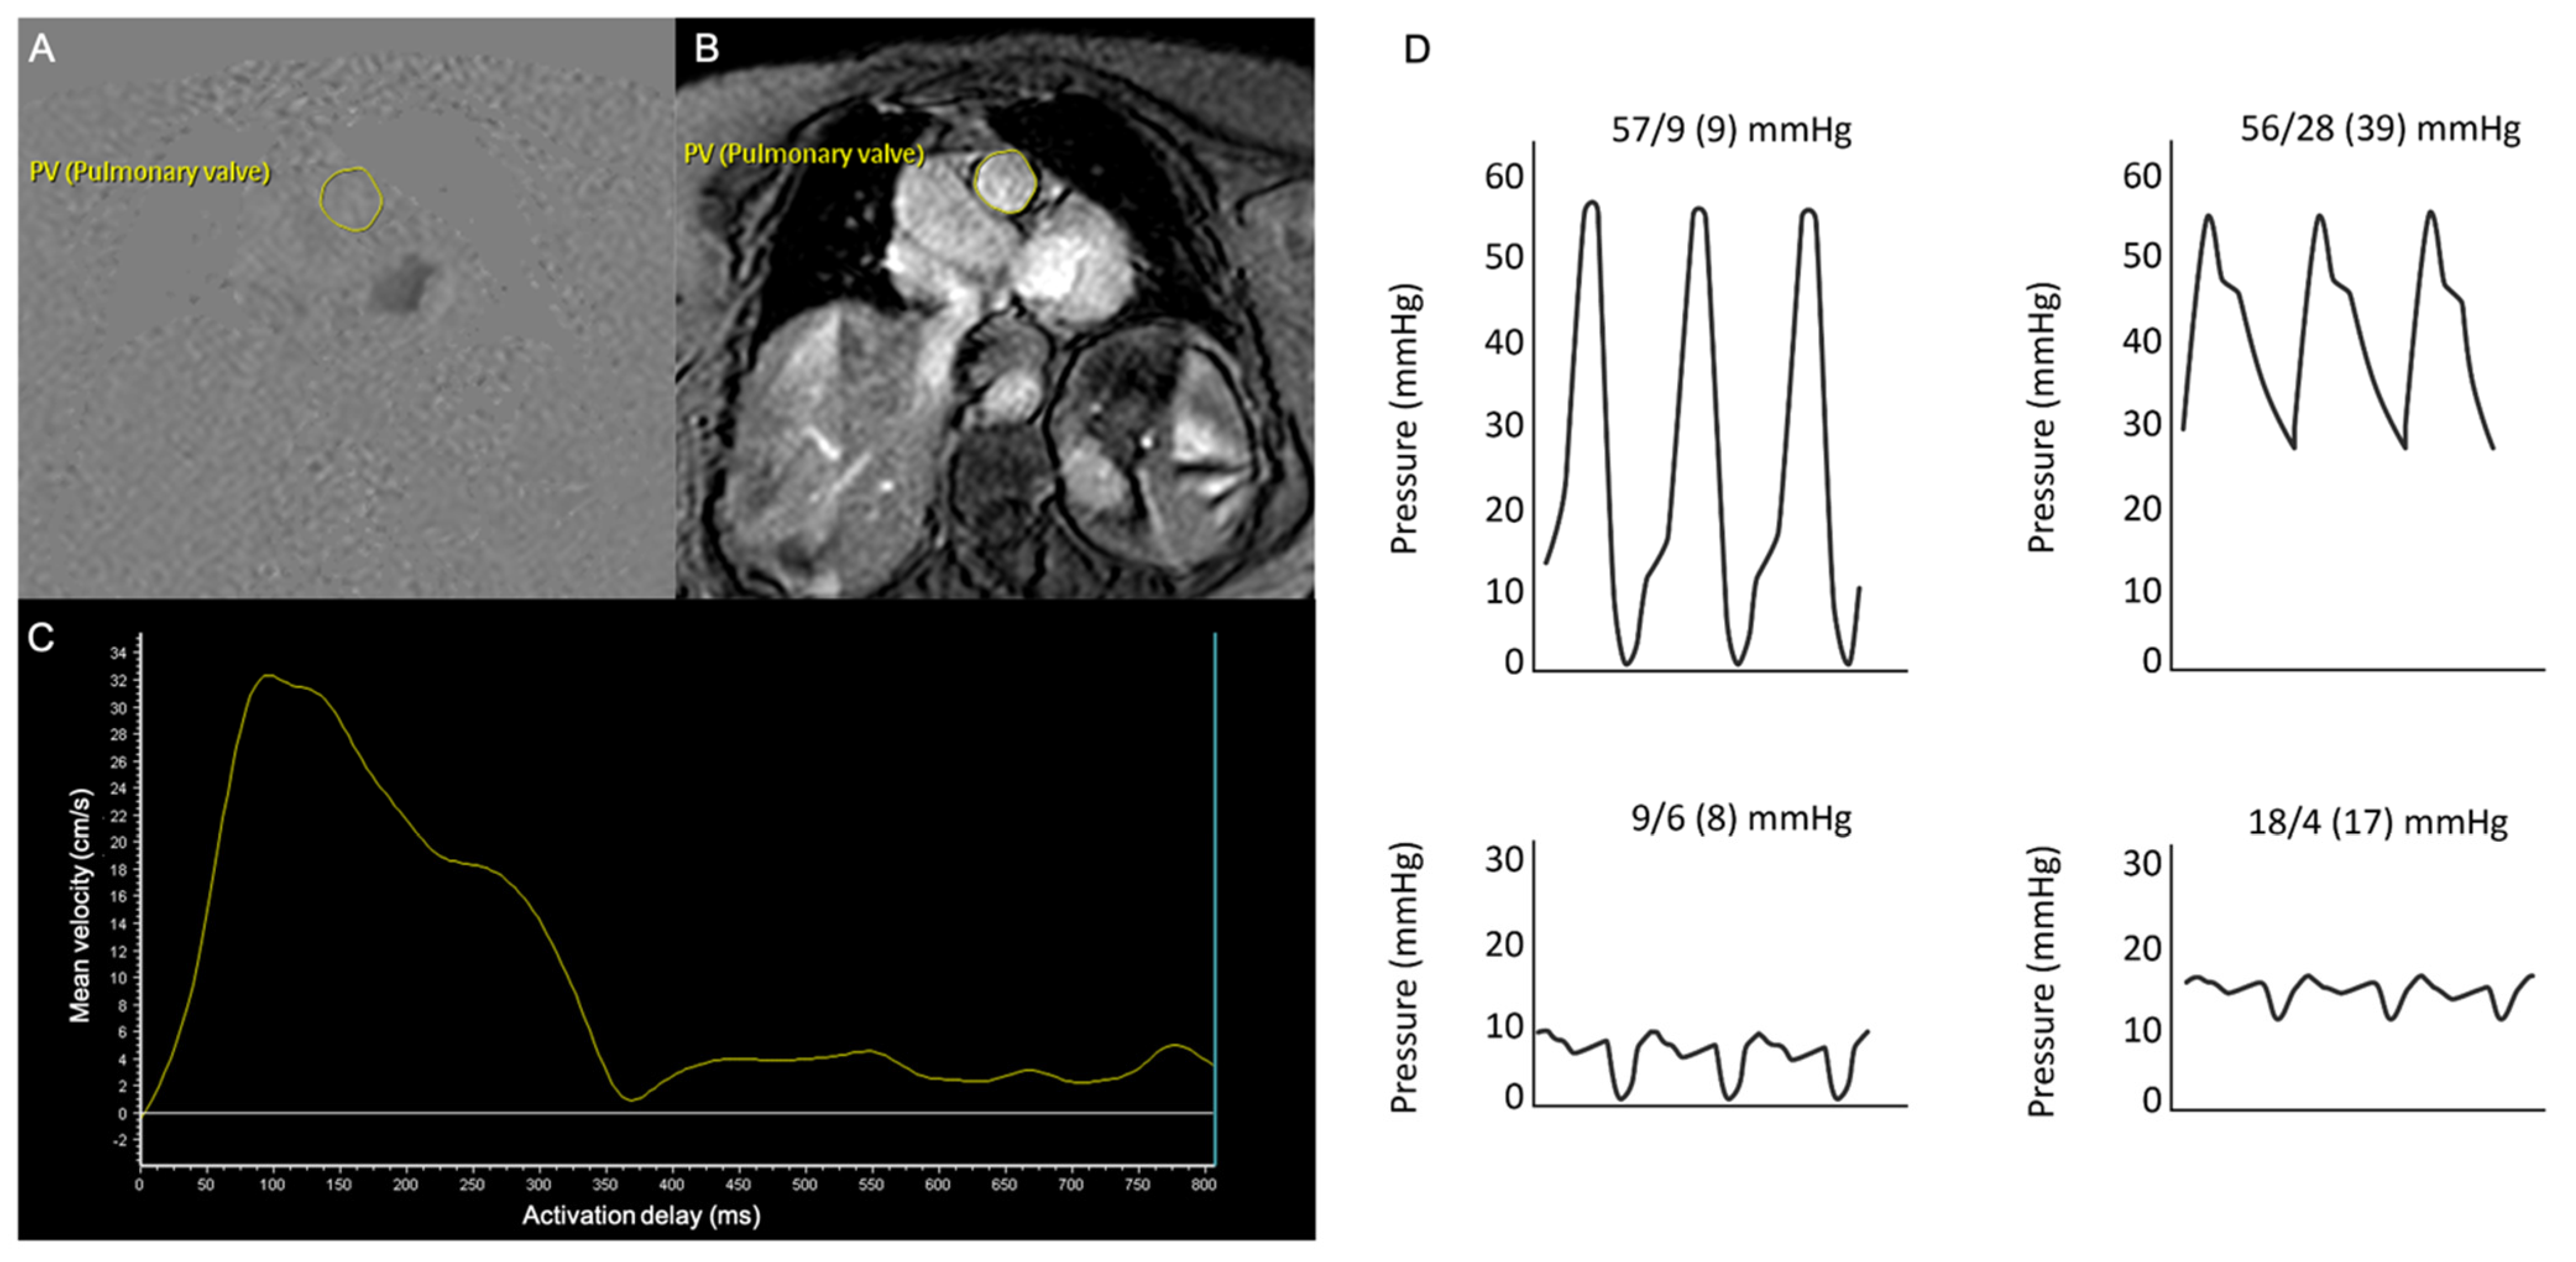

Pulmonary artery (PA) flow was assessed on slices perpendicular to the main PA, employing velocity-encoded gradient echo sequences. The axial section of the main PA was contoured in each cardiac phase to determine the PA area including minimum and maximum PA areas, as well as PA flow during the complete cardiac cycle. A dedicated software (Intellispace Portal 7.0, Philips Healthcare, Best, The Netherlands) calculated mvPA as the integral of the velocity in each of the voxels included within the PA outline over the complete cardiac cycle, Figure 1A–C. PA pulsatility was determined as [(maximum PA area − minimum PA area)/minimum PA area × 100], and pulmonary vascular resistance (PVR) was calculated by means of the formula: {PVR in Wood Units (WU) = 19.38 − [4.62 × Ln mvPA (cm/s)] − [0.08 × RV ejection fraction (RVEF)(%)]}, previously validated in PH patients [,]. Finally, RV to PC coupling ratio, which is the ratio between RV end-systolic maximal elastance (Emax, index of contractility) divided by PA effective elastance (Ea, index of arterial load), was estimated with the equation: [Emax/Ea = stroke volume(SV)/end-systolic volume(ESV)], validated by a prior study as an indicator of the RV–PC coupling state []. SV and ESV values in this equation were obtained by CMR.

Figure 1.

Cardiac magnetic resonance and right heart catheterization examinations of a representative patient. (A,B) Velocity-encoded gradient echo sequences on an axial section of the main PA. (C) Offline analysis of PA flow rate vs. time to calculate average and peak PA velocities. (D) Right chamber’s pressures determined by right heart catheterization.

Patients with mvPA ≤ 9 cm/s displayed greater LV hypertrophy and longer transmitral E-wave deceleration times. No significant differences in other echocardiographic parameters including RV function assessed by TAPSE, SPAP, or the TAPSE/SPAP ratio existed between patients with mvPA above and below 9 cm/s (Table 3). Notwithstanding, RVEF assessed by CMR was lower among patients with mvPA ≤ 9 cm/s. Patients with mvPA ≤ 9 cm/s also displayed enlarged RV end-systolic volumes, higher PVR and Ea/Emax estimated by CMR, and greater maximal and minimal PA areas, although no differences in PA pulsatility were observed. Regarding RHC parameters, there were no substantial differences in mean PA pressure, TPG, PVR, or PA compliance according to mvPA values, Table 3, Figure 1D.